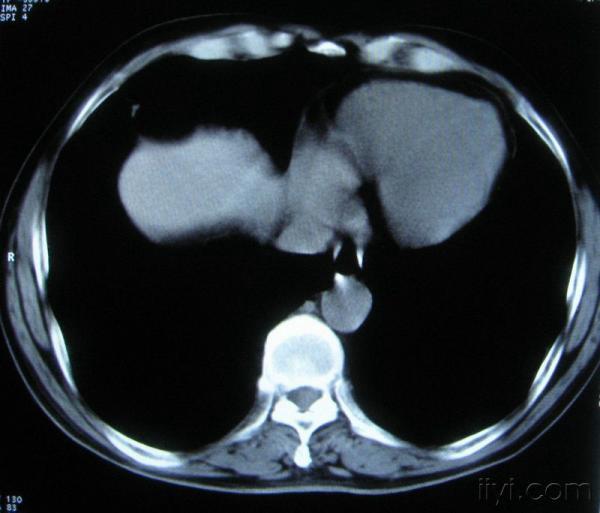

男。60岁,胸片示支气管炎治疗后复查CT。

根据位置考虑应该是淋巴结,密度不均,是因为肿大的淋巴结中心液化坏死

你指那个肯定是淋巴结,中央系坏死,这很常见,特别在双侧腹股沟会经常看到。这个双侧腋窝及纵隔见多发小淋巴结征。